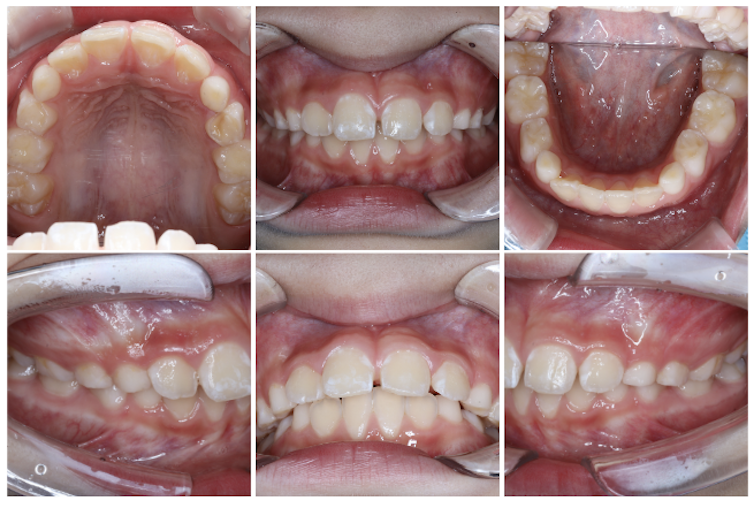

前歯のすき間(正中離開)を気にされていた親御様でしたが、定期検診の際に生え変わりとともに自然と閉じることもあることをお伝えしたところ、まずは経過を見ていくことになりました。

その後の定期検診で、過蓋咬合(上の前歯が下の前歯を深く覆いすぎてしまう噛み合わせ)が確認されたため、矯正についてお話しさせていただきました。その結果、マイオブレースによる矯正治療を8歳でスタートすることになりました。

前回症例紹介させていただいた男の子同様、

歯の重なりは少ないですが、噛み合わせの深さ(オーバーバイト)が5mmありました。

理想的な数値はだいたい2〜3mm程度が目安となります。

検査時に、過蓋咬合であることが数値上でも確認できました。